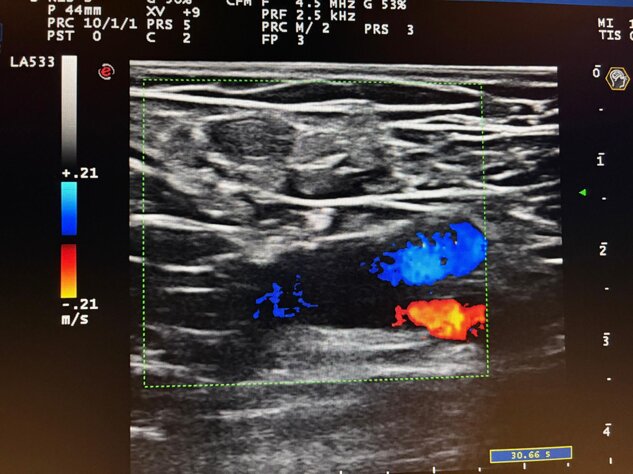

Ecocolordoppler

Incontinenza valvolare della vena safena interna alla coscia con reflusso venoso alle manovre di attivazione prossimale e distale.